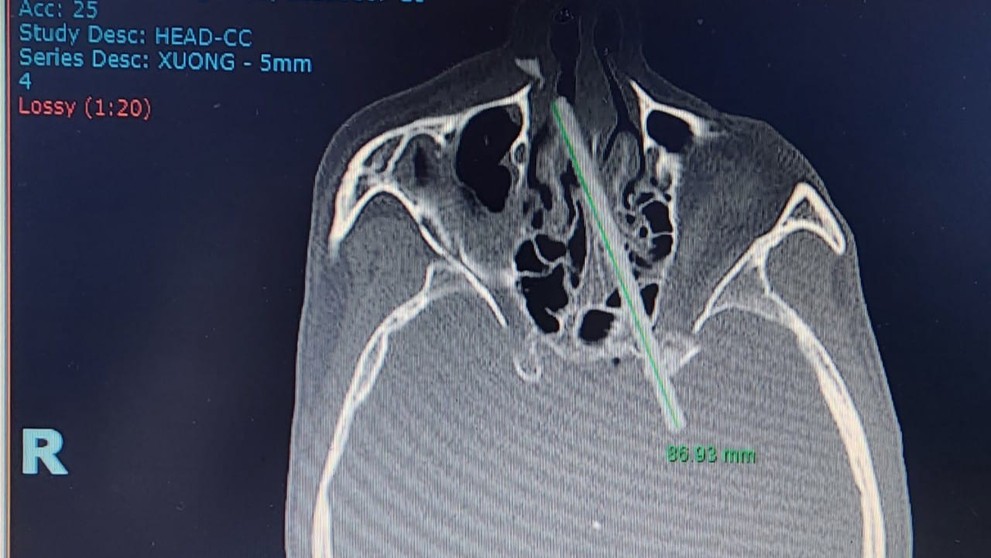

Snímka z počítačového tomografu. Zdroj: Vietnam - Cuba Friendship Hospital

Lekári z Vietnamu informovali o bizarnom prípade hraničiacom s medicínskym zázrakom. Ukázalo sa, že zdrojom bolesti hlavy, na ktorú sa niekoľko mesiacov sťažoval 35-ročný muž, sú jedálne paličky. Tie mal pacient cez nos vrazené do lebky, pričom tlačili na časť mozgu, informuje portál Vietnam.vn.

Ťažko uveriteľné tvrdenie podporili snímkou z počítačového tomografu (CT skenovania). Muž bol poriadne prekvapený, v prvom momente netušil, ako sa tam mohli paličky dostať. Potom si však spomenul, že sa pred piatimi mesiacmi zaplietol do bitky.